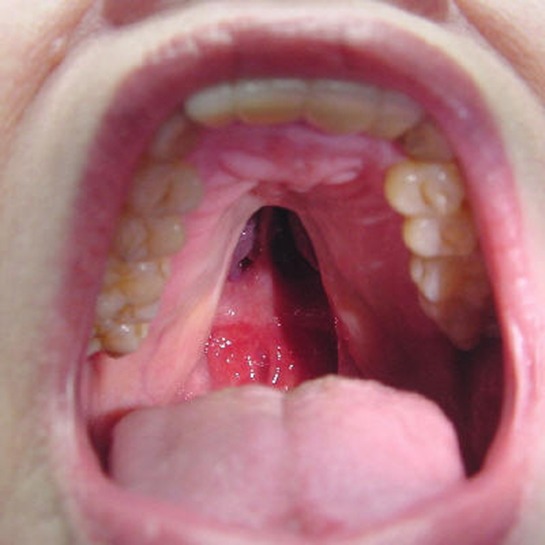

Damak Yarığı

Dudak yarıklarında bahsedildiği gibi yüzümüz embriyolojik dönemde orta hatta birleşmesi sırasında bir kesintiye uğrarsa damak yarıkları oluşabilir. Damak yarıkları başka deformiteler ile birlikte de görülebilir.

Damak yarıkları konuşma ve beslenme sorunlarına yol açabilmektedir. Erken yaşlarda ameliyatları mümkün olmadığı için ameliyat yaşına dek damak ateli ve özel biberonlar gibi ek önlemler gerektirirler. İdeal ameliyat 6 ay-24 ay arası önerilmektedir.